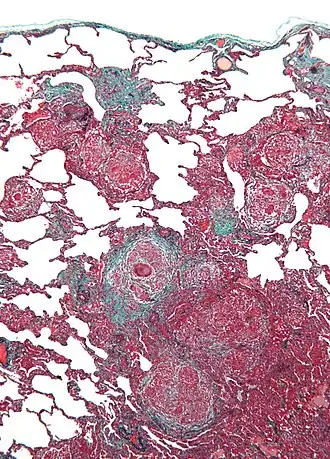

Biopsie de poumon.